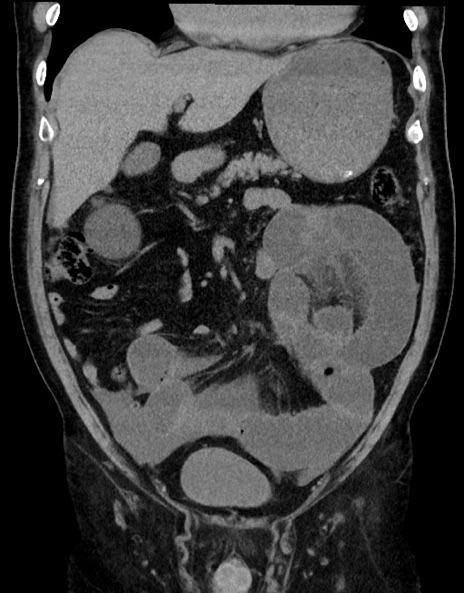

症例15(冠状断像)

【症例】70歳代男性

【主訴】腹痛

【現病歴】今朝から腹痛あり。全体的に痛い。特に左上の方。排ガスが今日はない。冷や汗が出る。

【既往歴】直腸癌術後

【身体所見】左側腹部〜上腹部に圧痛あり。腹膜刺激症状明らかなではない。軽度反跳痛。左下腹部に術後瘢痕あり。

【データ】WBC 7700、CRP 0.02